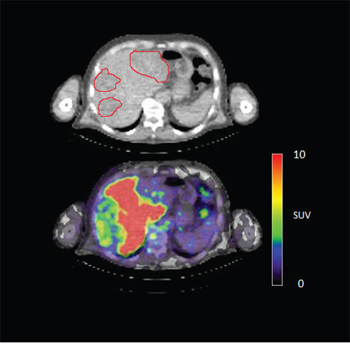

In 6 out of 10 patients, target lesions were visually assessed positive for 89Zr-cetuximab uptake. Figure 4A and 4B shows examples of visible 89Zr uptake in a metastatic lesion of the iliac bone (patient 8) and the lung (patient 10). In Figure 4C, another lung lesion in patient 10 shows no uptake. Most tumor lesions showed increasing uptake in time, indicating accumulation of cetuximab. SUVpeak of these lesions varied between 2.2–7.5 on day 6 p.i.. Figure 4D illustrates the photopenic aspect of liver metastases within normal liver tissue accumulating high amounts of 89Zr-cetuximab. Two of the 3 patients who were scanned at day 10 p.i. had visible 89Zr-cetuximab uptake. SUVpeak at day 10 increased compared to day 6 in patient 8 (from 7.3 to 10.3), but was comparable in patient 6 (3.17 and 3.36, Figure 4E Due to the physical half-life of 89Zr, image quality deteriorated over time, making day 6 p.i. the optimal scanning time point. Visually negative tumor sites had SUVmean of 1.0–1.9 at day 6 p.i. (Figure 5).

Figure 4D: 89Zr-cetuximab PET scan of patient 3 at day 6 p.i. illustrating high accumulation in healthy liver with relative photopenic area's in metastases.

Tumor uptake was initially evaluated by visual assessment, which implies contrast with background activity. The optimal scanning time point appears to be day 6 p.i., which is in line with literature and our expectations, based on the t½ of 89Zr [10]. The subsequently calculated SUVpeak at day 6 p.i. can discriminate between lesions with and without visible uptake (Figure 5) and suggests that a cut-off SUVpeak could be helpful in the determination of specific uptake versus background activity. Because a significant amount of the ID of 89Zr-cetuximab accumulated in the liver, hepatic metastases – although large enough for imaging purposes (diameter 4–14cm) - were unsuitable to evaluate tumor uptake as spill-over from uptake in adjacent normal liver tissue hampered adequate uptake evaluation of tumor sites. In addition, many large lesions have central necrosis with only a rim of viable tumor tissue, which is located immediately adjacent to healthy liver tissue accumulating very high levels of 89Zr cetuximab. As liver is a common metastatic site of mCRC, we have attempted to quantify uptake in hepatic metastases. In 6 target lesions in 5 patients we observed transient accumulation of 89Zr-cetuximab with highest levels at day 2 pi showing a comparable pattern as healthy liver tissue (data not shown). As the uptake pattern largely followed normal liver tissue, quantification of hepatic lesions seems to be unreliable due to spill-over of adjacent liver tissue. With the liver being a common metastatic site of mCRC this can limit the use of 89Zr-cetuximab as a treatment selection tool.